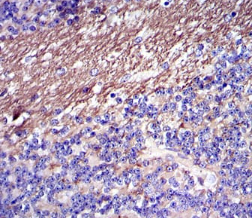

FGG Mouse Monoclonal antibody[4H9C9]

The protein encoded by this gene is the gamma component of fibrinogen, a blood-borne glycoprotein comprised of three pairs of nonidentical polypeptide chains. Following vascular injury, fibrinogen is cleaved by thrombin to form fibrin which is the most abundant component of blood clots. In addition, various cleavage products of fibrinogen and fibrin regulate cell adhesion and spreading, display vasoconstrictor and chemotactic activities, and are mitogens for several cell types. Mutations in this gene lead to several disorders, including dysfibrinogenemia, hypofibrinogenemia and thrombophilia. Alternative splicing results in two transcript variants encoding different isoforms.

Species Reactivity:    Human

Immunogen :   Purified recombinant fragment of human FGG expressed in E. Coli.

IHC    1/200 - 1/1000